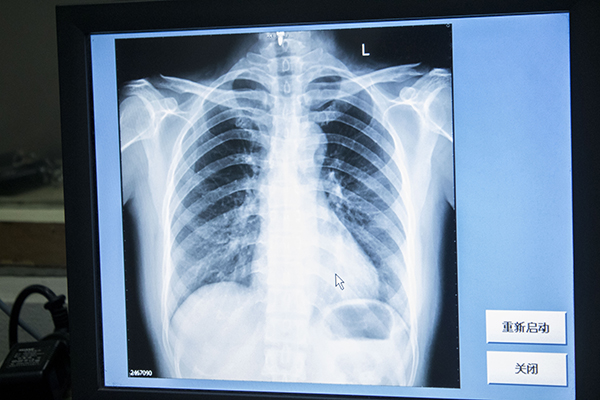

有很多女性不知从哪听说的,说这个的时候,人在屏幕后面是可以看得真真切切的,而这又是自己比较隐私的地方,如果是女的看的话,可能还好点,若是男的看的话,更会排斥了。其实这样的想法是错误的,别人能看到的也只是身体表现存在的,对于其他的情况并不知道,也并不会泄露自己的隐私,完全不用担心。

这其实和地铁过安检差不多,过地铁会检查你是否带有不能带的东西,而这个就是检查你的体内是否有不利于健康的物质。说白了,你的身体只是一个检测的对象,他们关注的是有没有问题,是身体内部各处的健康情况,并不是大家所以为的表面的皮肤,而且再退一步说,这样的影像也没有什么美感。